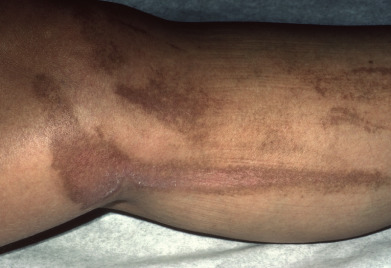

Cutaneous larva migrans demonstrates an erythematous serpiginous lesion. The worm is located ahead of the advancing border of the lesion, as the cutaneous reaction is a manifestation of a delayed-type immune response to the organism.